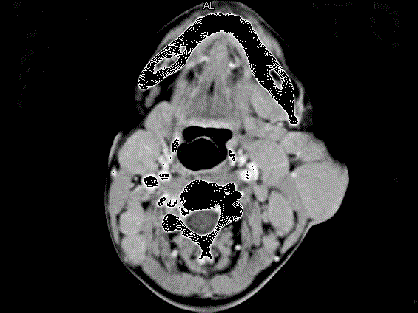

问题 女,25岁、发现双侧颈部肿块近10年,CT如图,最可能的诊断为 ( )

选项 A、淋巴结结核 B、淋巴结炎 C、淋巴瘤 D、转移癌 E、巨淋巴结增生症

答案 E